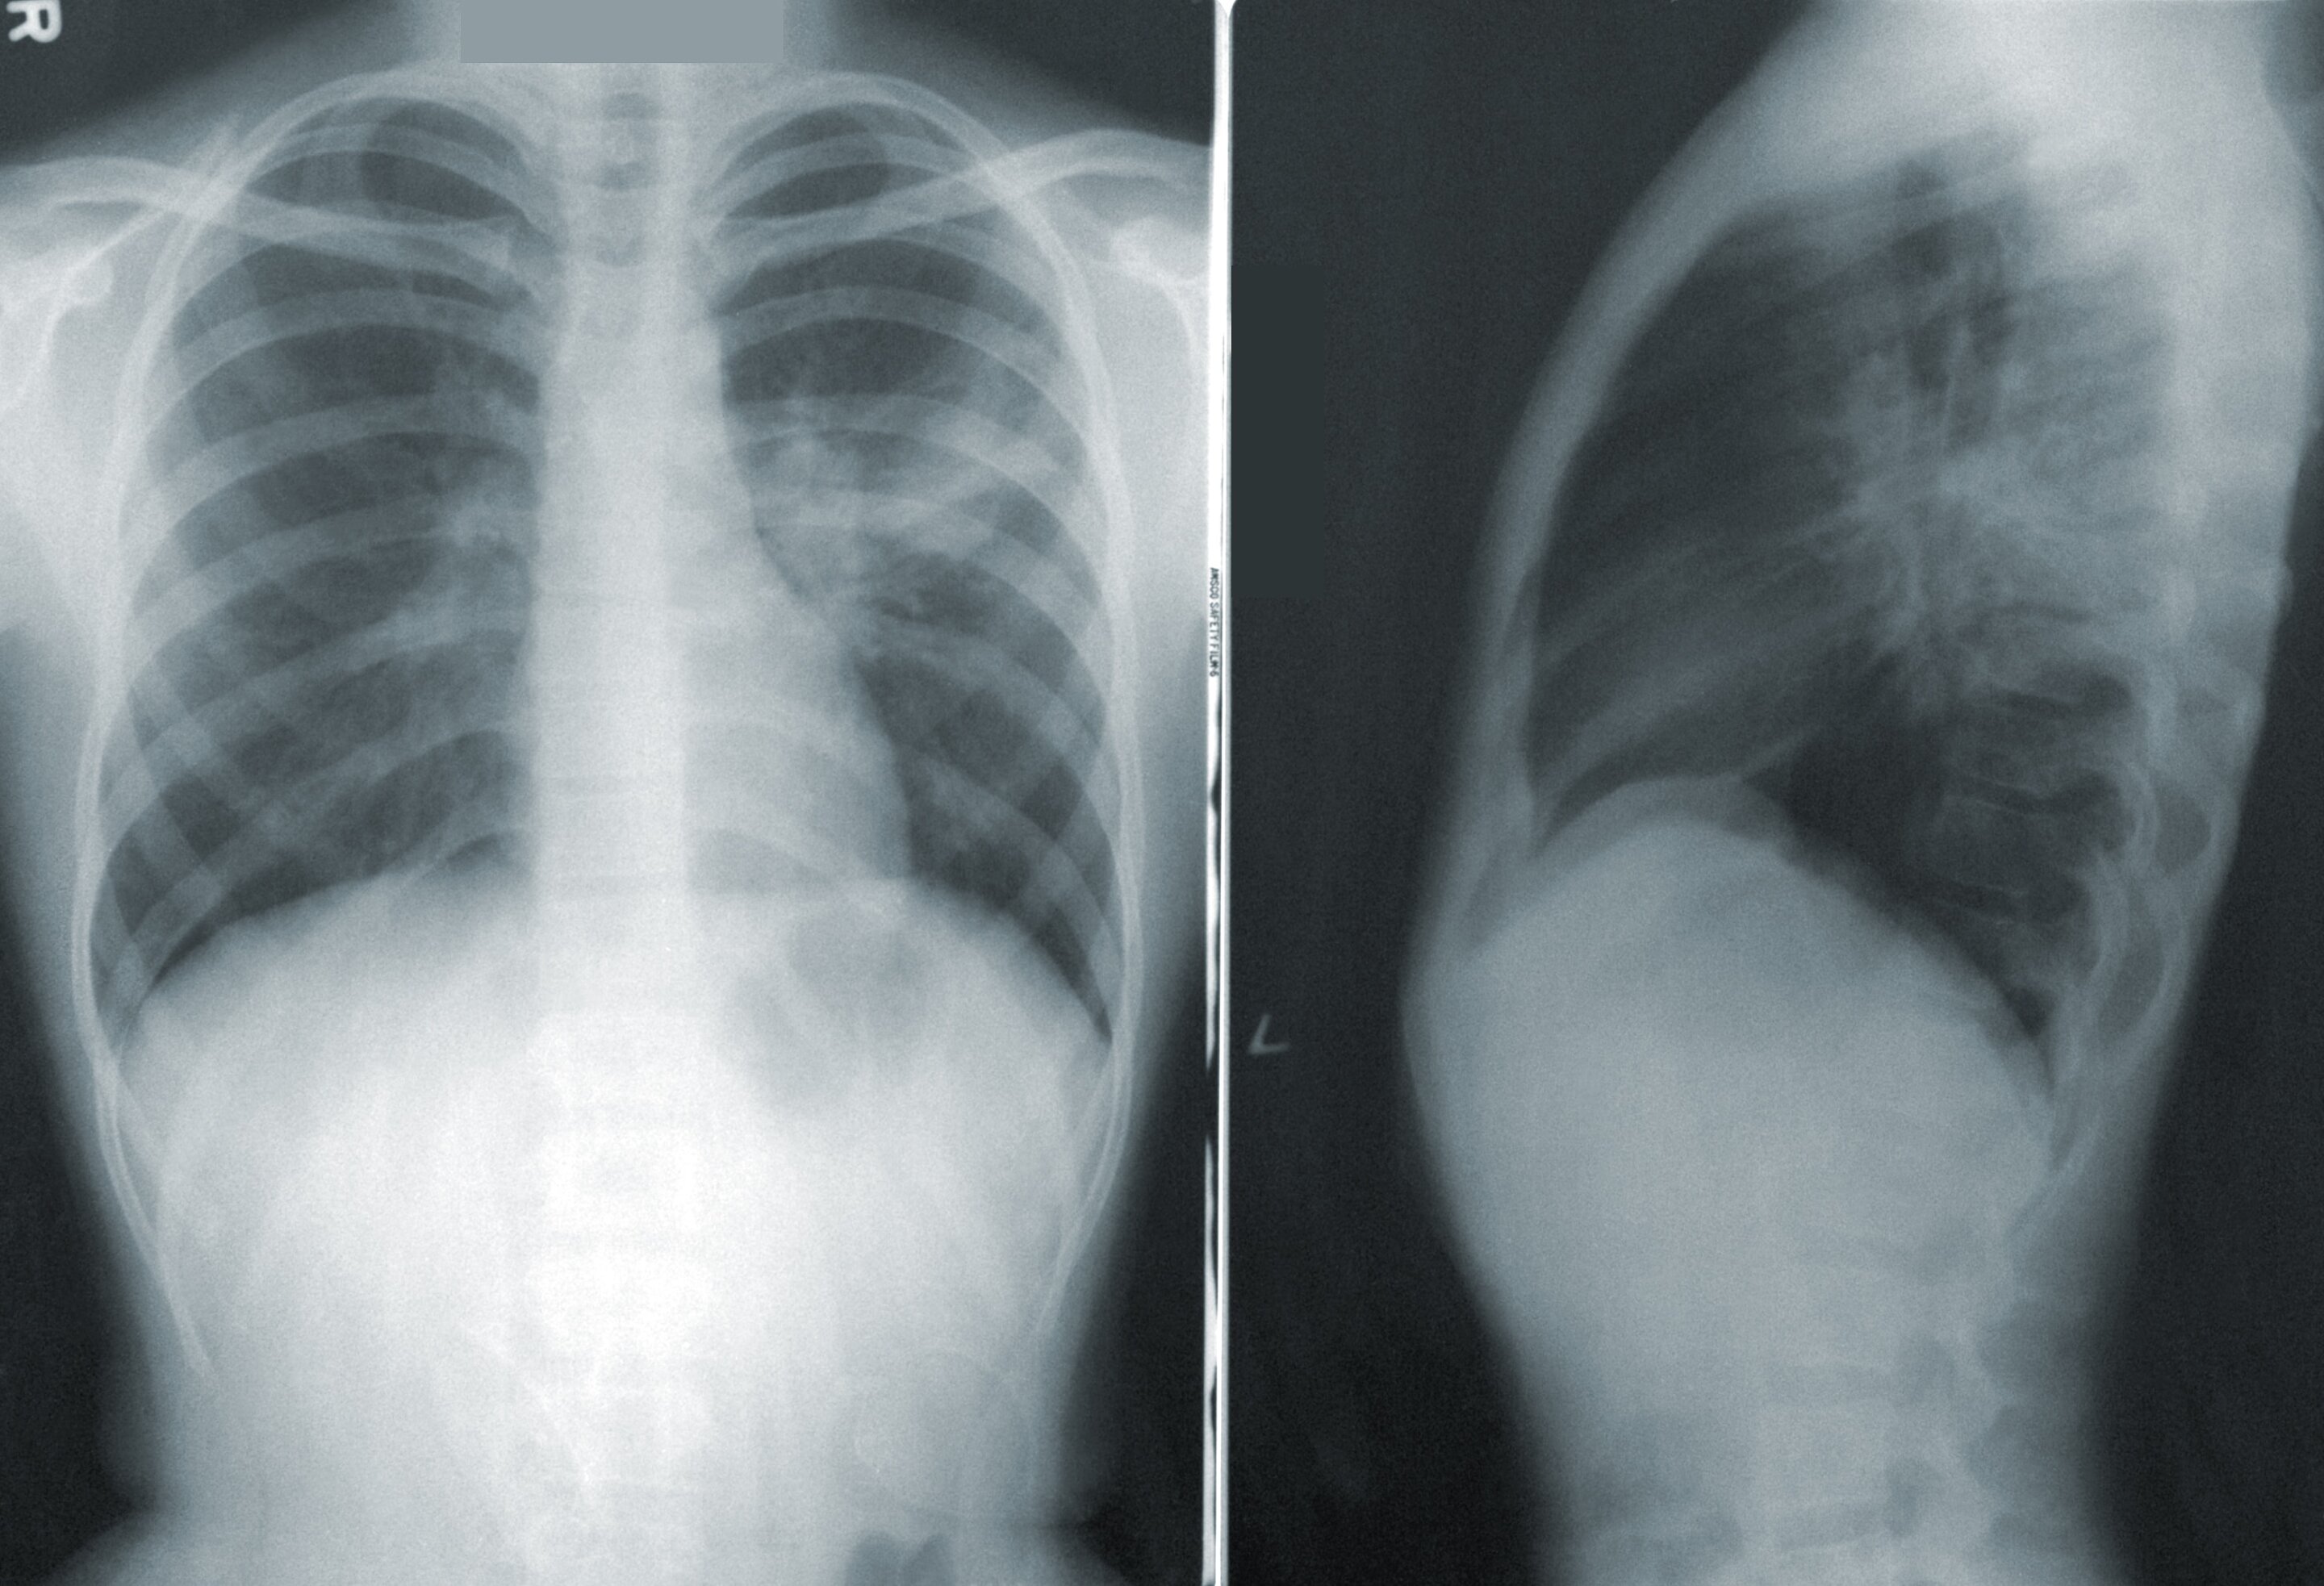

Uncovering Mechanisms of Lung Cancer Resistance to Common Therapy

Researchers have identified nongenetic mechanisms that contribute to the development of resistance to the anti-cancer medication sotorasib in lung cancer patients. The study found that tumor cells can become tolerant to the therapy without genetic mutations by manipulating the KRAS-sotorasib interaction network. However, long-term treatment can lead to genetic mutations that result in permanent resistance. The researchers also discovered that combining sotorasib with the FDA-approved anti-cancer therapy carfilzomib can address medication resistance in lung cancer cells. These findings provide insights into the complex interplay between genetic and nongenetic mechanisms in therapy resistance and offer potential therapeutic strategies for managing lung cancer patients.